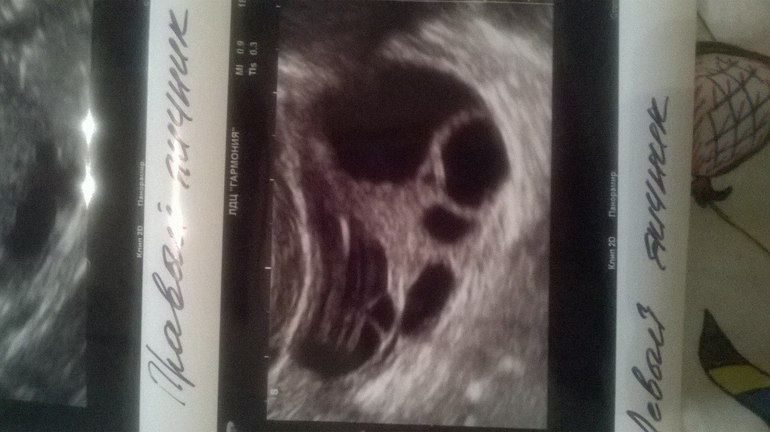

Фолликулометрияпосмотрите пожалуйста.может кто разбирается?благодарна за любое мнение. наверху

больше похоже на дф причем один такой хороший, большой

и внизу что-то полосатое, но обычно жт не такое.